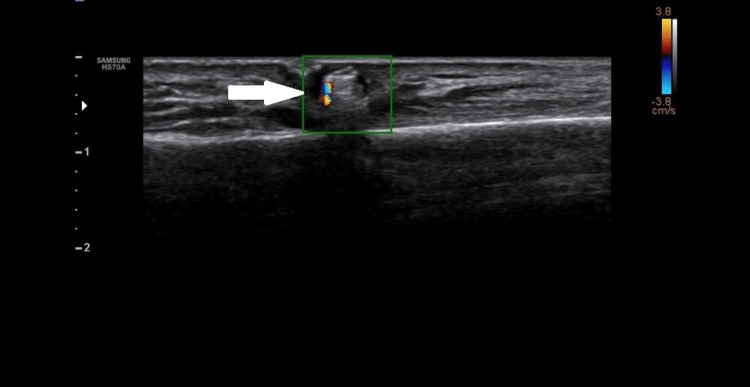

These foci had posterior acoustic shadowing and showed twinkling artefacts on a colour flow ultrasound (Figure 3).

Figure 3. Colour Doppler image showing twinkling artifact (arrow).

These echogenic foci were surrounded by hypoechoic hallow circumferentially and throughout their length.